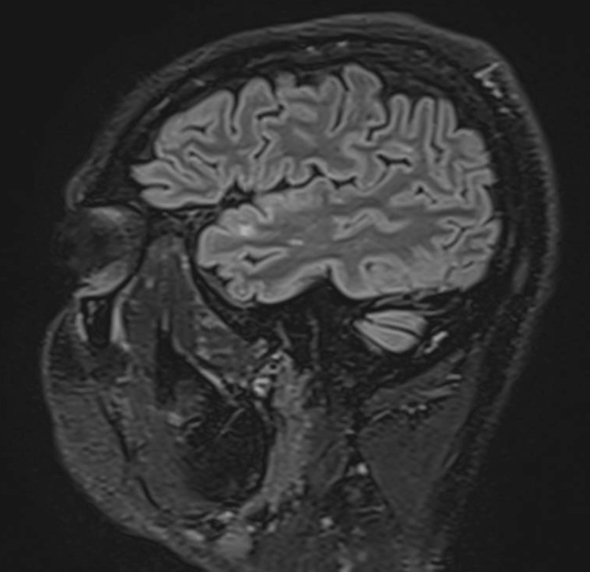

Le patient rapporte depuis trois semaines une diplopie lorsque ses deux yeux sont ouverts, qui disparaît à l’occlusion d’un œil. Il rapporte aussi une sensation d’instabilité à la marche avec une faiblesse de l’hémicorps gauche qui s’aggrave progressivement. Il ne décrit pas de sensation de rotation de lui-même ou de la pièce. Il a vu un ORL qui a prescrit un traitement symptomatique des vertiges, sans efficacité, raison pour laquelle il vous consulte.